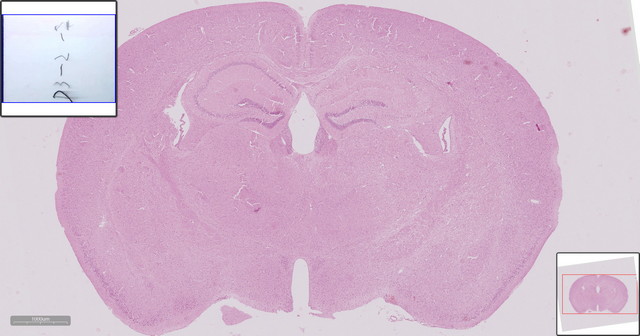

小鼠HE脑片